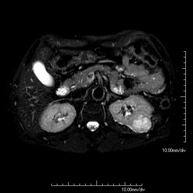

- RM d'Abdomen

Prova diagnòstica no invasiva que consisteix en l'obtenció d'imatges d'alta definició anatòmica de l'abdomen mitjançant l'ús d'un camp electromagnètic i ones de ràdio (amb un emissor i un receptor). No utilitza radiació ionitzant. En aquesta exploració s'inclouen el fetge, el pàncrees, la melsa, la via biliar, la vesícula biliar, les glàndules suprarenals, els ronyons, l'aorta abdominal, la vena cava inferior, l'estómac, el duodè, etc. En alguns casos caldrà emprar contrast paramagnètic (Gadolini) per caracteritzar les lesions. - RM Pelvis femenina

Prova diagnòstica no invasiva que consisteix en l'obtenció d'imatges d'alta definició anatòmica del fetge mitjançant l'ús d'un camp electromagnètic i ones de ràdio (amb un emissor i un receptor). No utilitza radiació ionitzant. Es realitza per estudiar qualsevol lesió localitzada en el fetge. Normalment es requereix l'ús de contrast paramagnètic (Gadolini) per caracteritzar les lesions. És necessari realitzat la prova en dejú (6 hores). - RM de Ronyons

Prova diagnòstica no invasiva que consisteix en l'obtenció d'imatges d'alta definició anatòmica d'ambdós ronyons mitjançant l'ús d'un camp electromagnètic i ones de ràdio (amb un emissor i un receptor). No utilitza radiació ionitzant. Es realitza per estudiar qualsevol lesió localitzada en ambdós ronyons. Normalment es requereix l'ús de contrast paramagnètic (Gadolini) per caracteritzar les lesions. - RM de Glàndules Suprarenals

Prova diagnòstica no invasiva que consisteix en l'obtenció d'imatges d'alta definició anatòmica del pàncrees mitjançant l'ús d'un camp electromagnètic i ones de ràdio (amb un emissor i un receptor). No utilitza radiació ionitzant. Requereix dejuni de 6 hores. Permet un estudi específic pancreàtic, tant de la part glandular com dels conductes de drenatge dels sucs pancreàtics, amb una alta definició tissular. També s'estudien els vasos pancreàtics i les estructures adjacents com són la vena porta, l'artèria i la vena esplènica, el greix peri-pancreàtic, l'aorta abdominal, la vena cava inferior, etc. En la majoria dels casos s'empra contrast paramagnètic (Gadolini) per a una millor definició tissular. Aquesta prova està especialment indicada en pacients amb sospita de lesions pancreàtiques, en pacients amb neoplàsia pancreàtica coneguda com l'estudi o mapa abans de la cirurgia, en pacients amb pancreatitis crònica o aguda, etc. - URO-RM